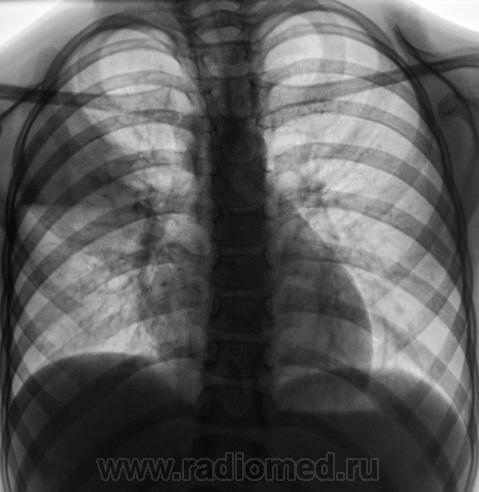

Ребёнок направлен на рентгенографию ОГК с диагнозом "Правосторонняя пневмония".

Согласен : в S2, S3 в/доли справа - инфильтрация в паренхиме; возможно, осумкование жидкости в м/долевой щели...

Как по мне, так и добавить больше нечего, инфильтрация распространяется на С3 и частично на  С2. Классическая пневмония. Лечим дней 10-14 и делаем контроль в двух пр.

в S2, S3 в/доли справа - инфильтрация в паренхиме; возможно, осумкование жидкости в м/долевой щели...

или просто реакция плевры?

Ну если интерес есть, почему же и не поговорить?wink Итак, по первому случаю у меня такие мысли: изменения по типу перисциссурита, -это факт. Но! Обратите внимание, коллеги, на совершеннейшее спокойствие корня! У детей при такой массивной инфильтрации лимфоузлы должны реагировать хоть небольшим, но увеличением. Конечно, я не знаю клиники, контактов ребёнка, анализов, проведённых тестов на твс, я достоверно говорить , следовательно, не могу. Но мы видим прекрасную R-динамику от неспецифического лечения. Да, потом подключились фтизиатры, но издавна ведь известно, что и противотуберкулёзные препараты могут подавлять чувствительную к ним неспецифическую флору. В остатке имеем малые изменения в виде локального фиброза( и то с натяжкой). И ретроспективно сказать, было ли сочетание малых форм твс с пневмонией просто по динамике на снимках сложно. Но группа R+ однозначно.